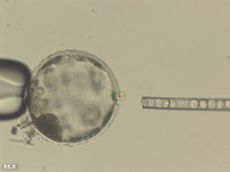

Human-Pig Chimeras Created, Could One Day Aid in Organ Transplants

Researchers recently succeeded in making embryos that contained both pig and human and pig cells.